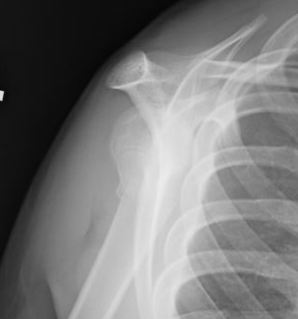

Case: 18 year old boy

Initial xray 18 month xray